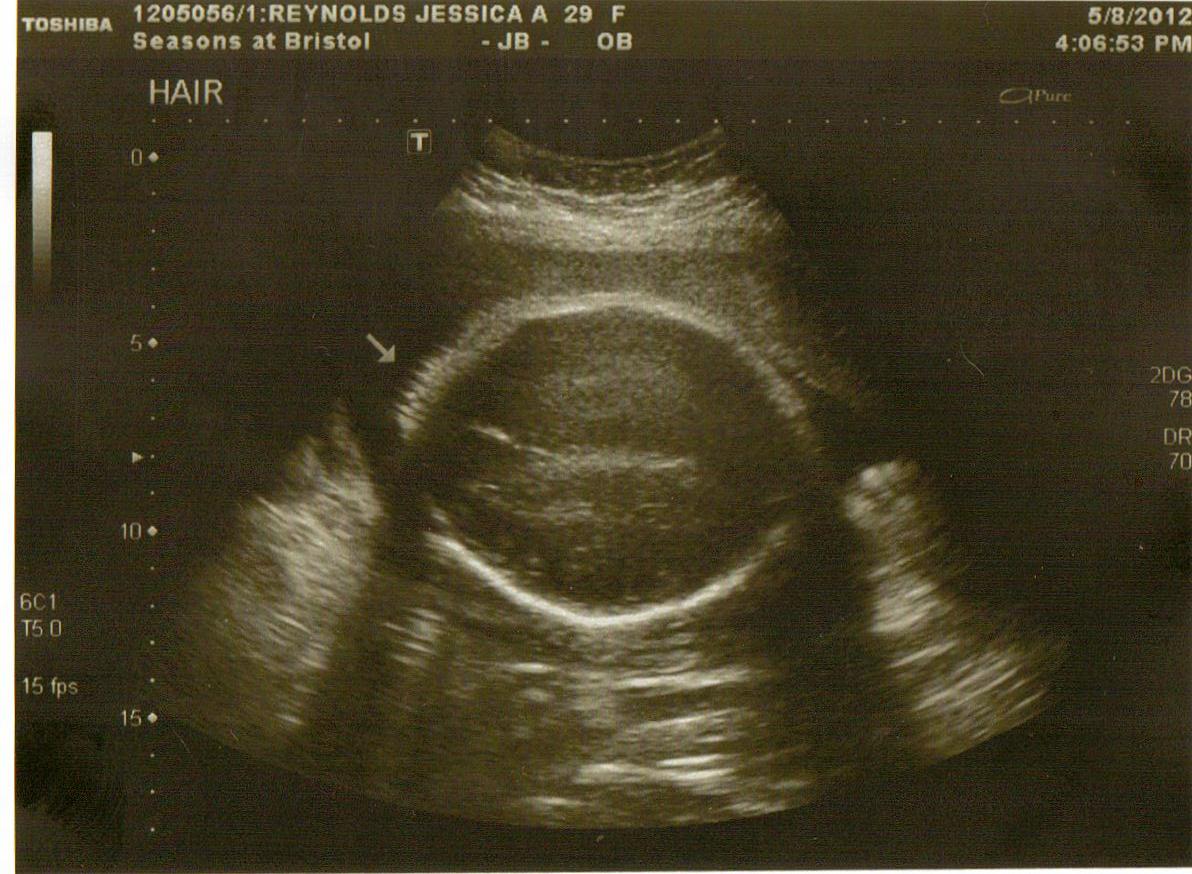

From ultrasoundfeminsider.com

Normal 33 week baby ultrasound. Ultrasoundfeminsider Baby Head Down Position At 33 Weeks It’s almost go time, so baby is likely positioned head down, or will be very soon. This is the ideal and safest position for delivery. Know the different baby positions. Some of the most common signs that your baby may be in a breech position include the presence of what feels like the baby’s head above your bellybutton, a head. Baby Head Down Position At 33 Weeks.